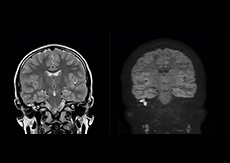

“We also love MultiVane XD for motion reduction in imaging. We find this a huge step forward. We use it in the head, and of course in the upper abdomen, and the images are outstanding most of the time. And it can be combined with dS SENSE parallel imaging for speed.” “We have compared image quality of FLAIR with MultiVane XD versus FLAIR without MultiVane XD. In 15 of the 40 patients studied, we saw motion artifacts on plain FLAIR brain images. The FLAIR images with MultiVane XD were motion-free in 39 of 40 patients and showed slight motion artifacts in only one patient.”